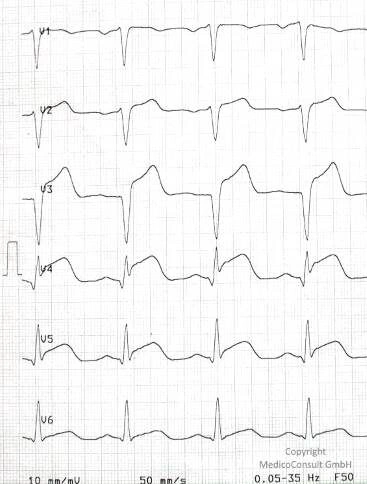

Restriktive Kardiomyopathie

Die restriktive Kardiomyopathie (RCM) ist eine schweren Funktionsstörung des Herzens (Diastole) durch zunehmend bewegungseingeschränkte Wände der Herzkammern (Ventrikel). Es kommt zu einer Herzinsuffizienz mit niedrigem Blutdruck und Ödemen.

Therapie des Herzinfarkts

Die Therapie des Herzinfarkts hat akute und langfristige Ziele. Zunächst ist die Wiederherstellung des Blutflusses in den Herzkranzgefäßen und somit die Reperfusion des Herzmuskels erforderlich. Dies muss so schnell wie möglich geschehen, um einer irreversiblen Schädigung des Herzmuskels vorzubeugen.